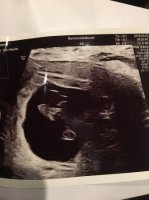

Så herligHar vært på TUL, å der var denne lille søte reka.Jeg er så glad, nå kan jeg endelig senke skuldrene (litt)

Hun målte meg nøyaktig like langt som jeg var, å det var jo bra

Awww rørende å se den lille for første gang ❤Har vært på TUL, å der var denne lille søte reka.Jeg er så glad, nå kan jeg endelig senke skuldrene (litt)